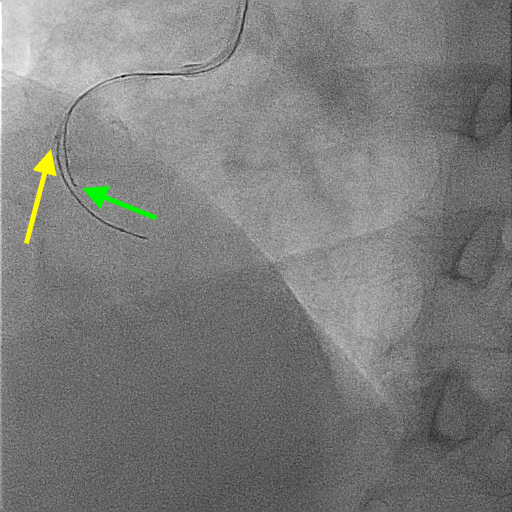

A 51-year-old man presented with stable angina and previously failed right coronary artery (RCA) CTO PCI. During RCA CTO PCI (Figure 1), the wire was inserted into the extraplaque space (Figure 2, Video 1). Intravascular ultrasound (IVUS) showed a hematoma (Figure 3A, Video 2). Live 3-dimensional tip detection IVUS wiring was successful (Figure 4, Video 3). A FineCross microcatheter (Terumo) was placed over the first wire into the extraplaque space and blood was withdrawn by connecting a negative indeflator to the microcatheter. Stents were deployed (Figure 5) and postdilated. Post-IVUS showed almost complete resolution of the hematoma (Figure 3B, C; Video 4) with good results (Figure 6, Video 5).